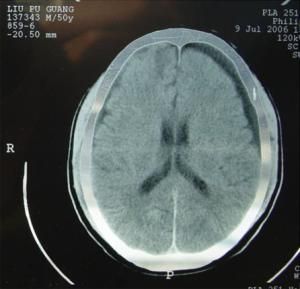

1.CT掃描 顯示為新月形低密度影,CT值7Hu左右,近於腦脊液密度。占位表現較硬膜下血腫輕。硬膜下積液可發展為硬膜下血腫,可能系再出血所致,其CT值可升高。

2.MRI 無論急性或慢性硬膜下積液,在MRI上均呈新月形長T1與長T2信號,信號強度接近於腦脊液。